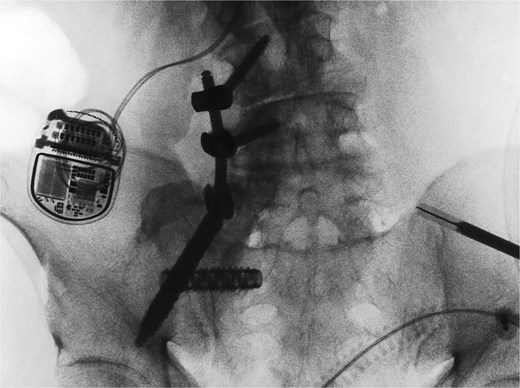

A CT of the pelvis showed significant hyperostosis along the anterior right SI joint and a pseudoarthrosis between the L5 transverse process and the sacral ala that was osteoblastic-appearing in nature (Fig. 1). A SPECT-CT demonstrated increased uptake along the same area, suggestive of inflammatory degenerative changes (Fig. 2).

Coronal CT pelvis (left) and axial (right) demonstrated hyperostosis along the right SI joint suggestive of an osteoblastic lesion between the L5 transverse process and sacral ala (arrows).